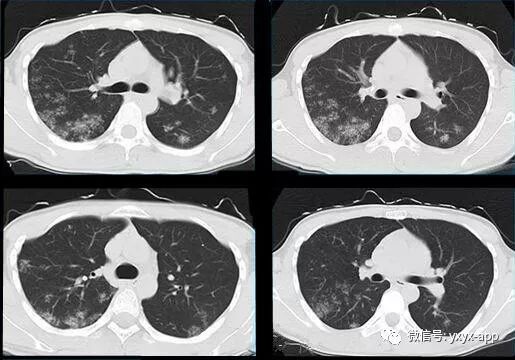

【病例】肺泡蛋白沉积症1例CT影像表现

【基本资料】男,19岁

【主诉】体检胸片发现肺部阴影半月余,

【现病史】半月前体检发现肺部阴影,行CT检查,抗炎后复查,无明显吸收、好转

10天后复查

评论:两肺斑片状磨玻璃影,与周围组织分界清楚,呈“地图样”表现,部分病变延伸至胸膜下,部分小叶间隔增厚,气管居中,肺门及纵膈未见肿大淋巴结影,未见胸腔积液。患者青年男性,临床症状轻微影像表现严重,抗炎治疗无效。考虑肺泡蛋白沉积症

【结果】肺泡灌洗病理证实:肺泡蛋白沉积症